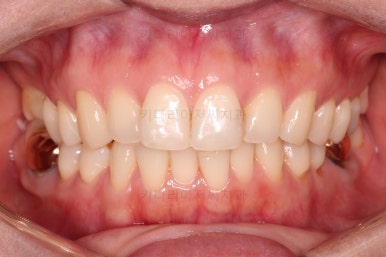

치료 종료시의 모습인데요.

임플란트가 잘 들어갔고 아래 앞니도 원하는 모습으로 잘 배열이 되었습니다.

부산치아교정비용 전후 비교해 볼게요.

치료기간은 임플란트의 안정성 때문에 길어지긴 했으나 사실상 내원횟수는 그리 많지 않으셨고, 교정장치가 눈에 보이는 기간은 7개월정도 밖에 안되었기 때문에 크게 문제되지는 않았던 것 같습니다.

여러 가지가 다 잘 마무리 되었습니다.